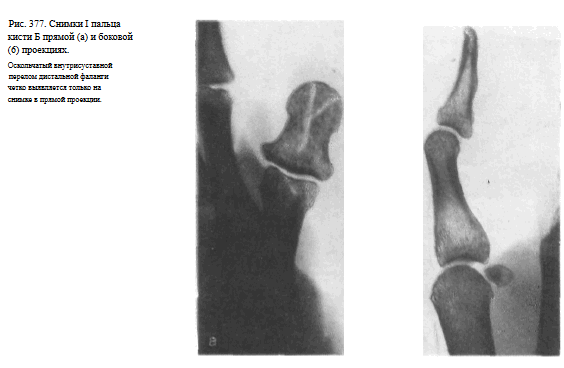

Снимок I пальца в боковой проекции. I палец прилежит к кассете лучвым (наружным) краем.

Остальные пальцы слегка согнуты, опираются концами на перекрытую листом просвинцованно резины уже проэкспонированную половину кассеты.

Пучок рентгеновского излучения направлен на проекцию пястно-фалангового сустава (рис. 375).

На рентгенограмме выявляются тыльная и ладонная поверхности фаланг и частично I пястной кости.

Видны наслаивающиеся друг на друга сесамовидные кости рядом с головкой I пястной кости (рис. 376). Снимки необходимо выполнять в двух взаимно перпендикулярных проекциях (рис. 377, а, б).